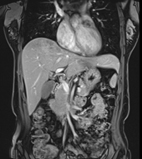

磁振造影清晰呈現腹腔內實質的器官如:肝臟、脾臟、胰臟、腎臟…等,提供醫師在腫瘤診斷、評估與治療上重要的資訊

MRI能分辨許多不同的肝臟病灶,對於檢測原發性肝臟腫瘤和由其他器官轉移到肝臟的腫瘤,也有優異的鑑別能力。MRI可以幫助區分大多數良性與惡性的肝臟腫瘤,並偵測惡性腫瘤如肝細胞癌(Hepatoma),對於周邊正常組織的侵犯程度,有助於疾病診斷和腫瘤治療的評估。

胰臟位於腹部深處,超音波有時不容易看清楚,而MRI在胰臟成像方面則非常清晰,有機會檢測出微小的腫瘤病灶或其他異常。由於MRI可顯示胰臟病變的特徵與型態,有助於醫師區分良、惡性腫瘤,並且可以一併評估胰臟周圍的血管,判斷胰臟附近的組織,是否有受到腫瘤侵犯,這些詳細的資訊對於手術計劃相當重要。